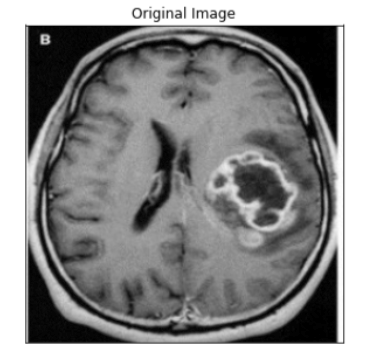

Now test the model in the test set.

#Test Set

ind = 1

display_image(dataset_test, ind)

predict_and_plot_differences(dataset_test, ind)

ind = 0

As you can see we are getting pretty good accuracy.